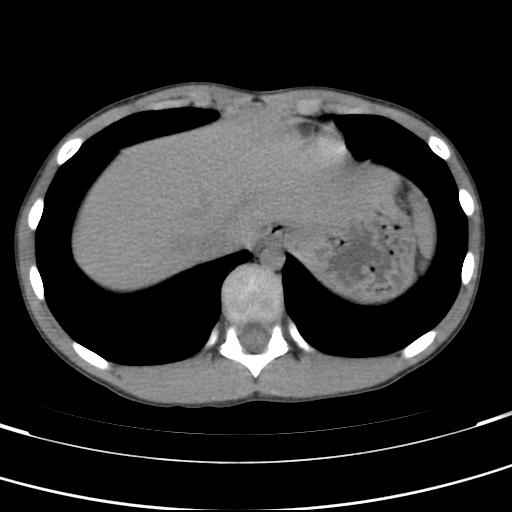

标题: PED3157:左肾缺如,请教脾脏的改变?、、

男孩,9岁。胃部不适。

脾脏位于左侧,但数个脾脏呈分离状态,左肾缺如,右肾代偿肥大。考虑多脾综合征。